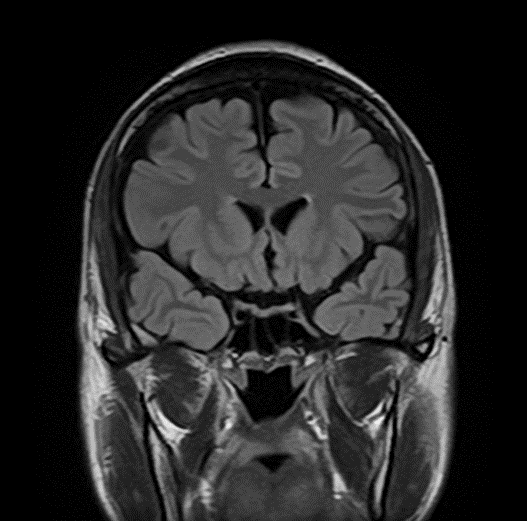

ボーっとしている・歩行ふらつきを認め受診した例

一カ月前に転倒し頭部打撲。転倒当日CT検査を行い異常なし。転倒から一カ月後から返答がうわのそら、さらに歩行時のふらつきが目立つようになり受診

→に血腫を認める。血腫による圧迫により健常側に見られる脳のしわ(→)が潰れている。

→に厚い血腫を認める

穿頭(せんとう)血腫除去術後

血腫は除去されている

術後から症状は改善され、退院。